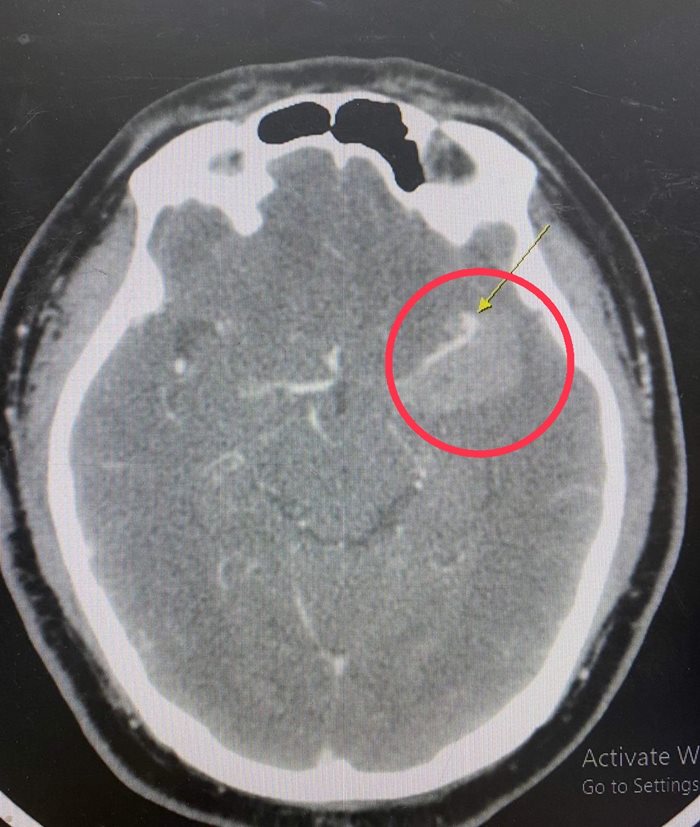

ผลเอกซเรย์น่าตกใจ คนไข้มีเส้นเลือดในสมองโป่งพอง ต้องผ่าตัดด่วน

จากภาพรังสี พบว่า คนไข้มีเส้นเลือดในสมองโป่งพอง เส้นเลือดปริแตก มีเลือดกระจายไปสู่เนื้อสมอง ขยายเป็นวง รอบเส้นเลือดที่แตก จึงปรึกษากับศัลยแพทย์ระบบประสาทและสมอง เพื่อเตรียมการผ่าตัดในทันที ก่อนที่เลือดออกในเนื้อสมองมากขึ้น จะส่งผลให้เนื้อสมองขาดเลือดเป็นวงกว้างไปมากกว่านี้